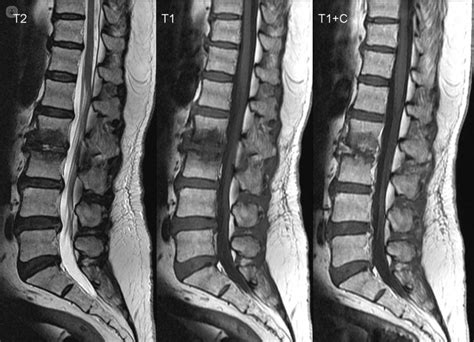

Resonancia Magnética Lumbar, Cervical o Dorsal

Este estudio se centra en obtener imágenes detalladas de la columna vertebral, incluyendo huesos, discos intervertebrales, médula espinal y estructuras nerviosas circundantes. Es fundamental para el diagnóstico de hernias discales, estenosis espinal, tumores y otras afecciones de la espalda.

La resonancia magnética espinal es un procedimiento no invasivo que permite visualizar con gran precisión los tejidos blandos, los discos, las vértebras y las estructuras nerviosas. Es de gran utilidad para diagnosticar patologías como hernias discales, estenosis espinal, tumores, aplastamientos y fusiones vertebrales, así como afectaciones de la médula espinal.